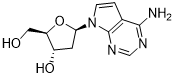

馬鞍山致研生物醫(yī)藥科技有限公司成立于馬鞍山市鄭浦港新區(qū)現(xiàn)代產(chǎn)業(yè)園。公司專(zhuān)注于生物小分子、醫(yī)藥中間體相關(guān)產(chǎn)品的研發(fā)和生產(chǎn),產(chǎn)品主要包括DNA亞磷酰胺單體、RNA亞磷酰胺單體、特殊單體以及按照客戶(hù)要求定制的RNA和DNA,并且公司提供定制合成等方面的研究服...

馬鞍山致研生物醫(yī)藥科技有限公司成立于馬鞍山市鄭浦港新區(qū)現(xiàn)代產(chǎn)業(yè)園。公司專(zhuān)注于生物小分子、醫(yī)藥中間體相關(guān)產(chǎn)品的研發(fā)和生產(chǎn),產(chǎn)品主要包括DNA亞磷酰胺單體、RNA亞磷酰胺單體、特殊單體以及按照客戶(hù)要求定制的RNA和DNA,并且公司提供定制合成等方面的研究服...